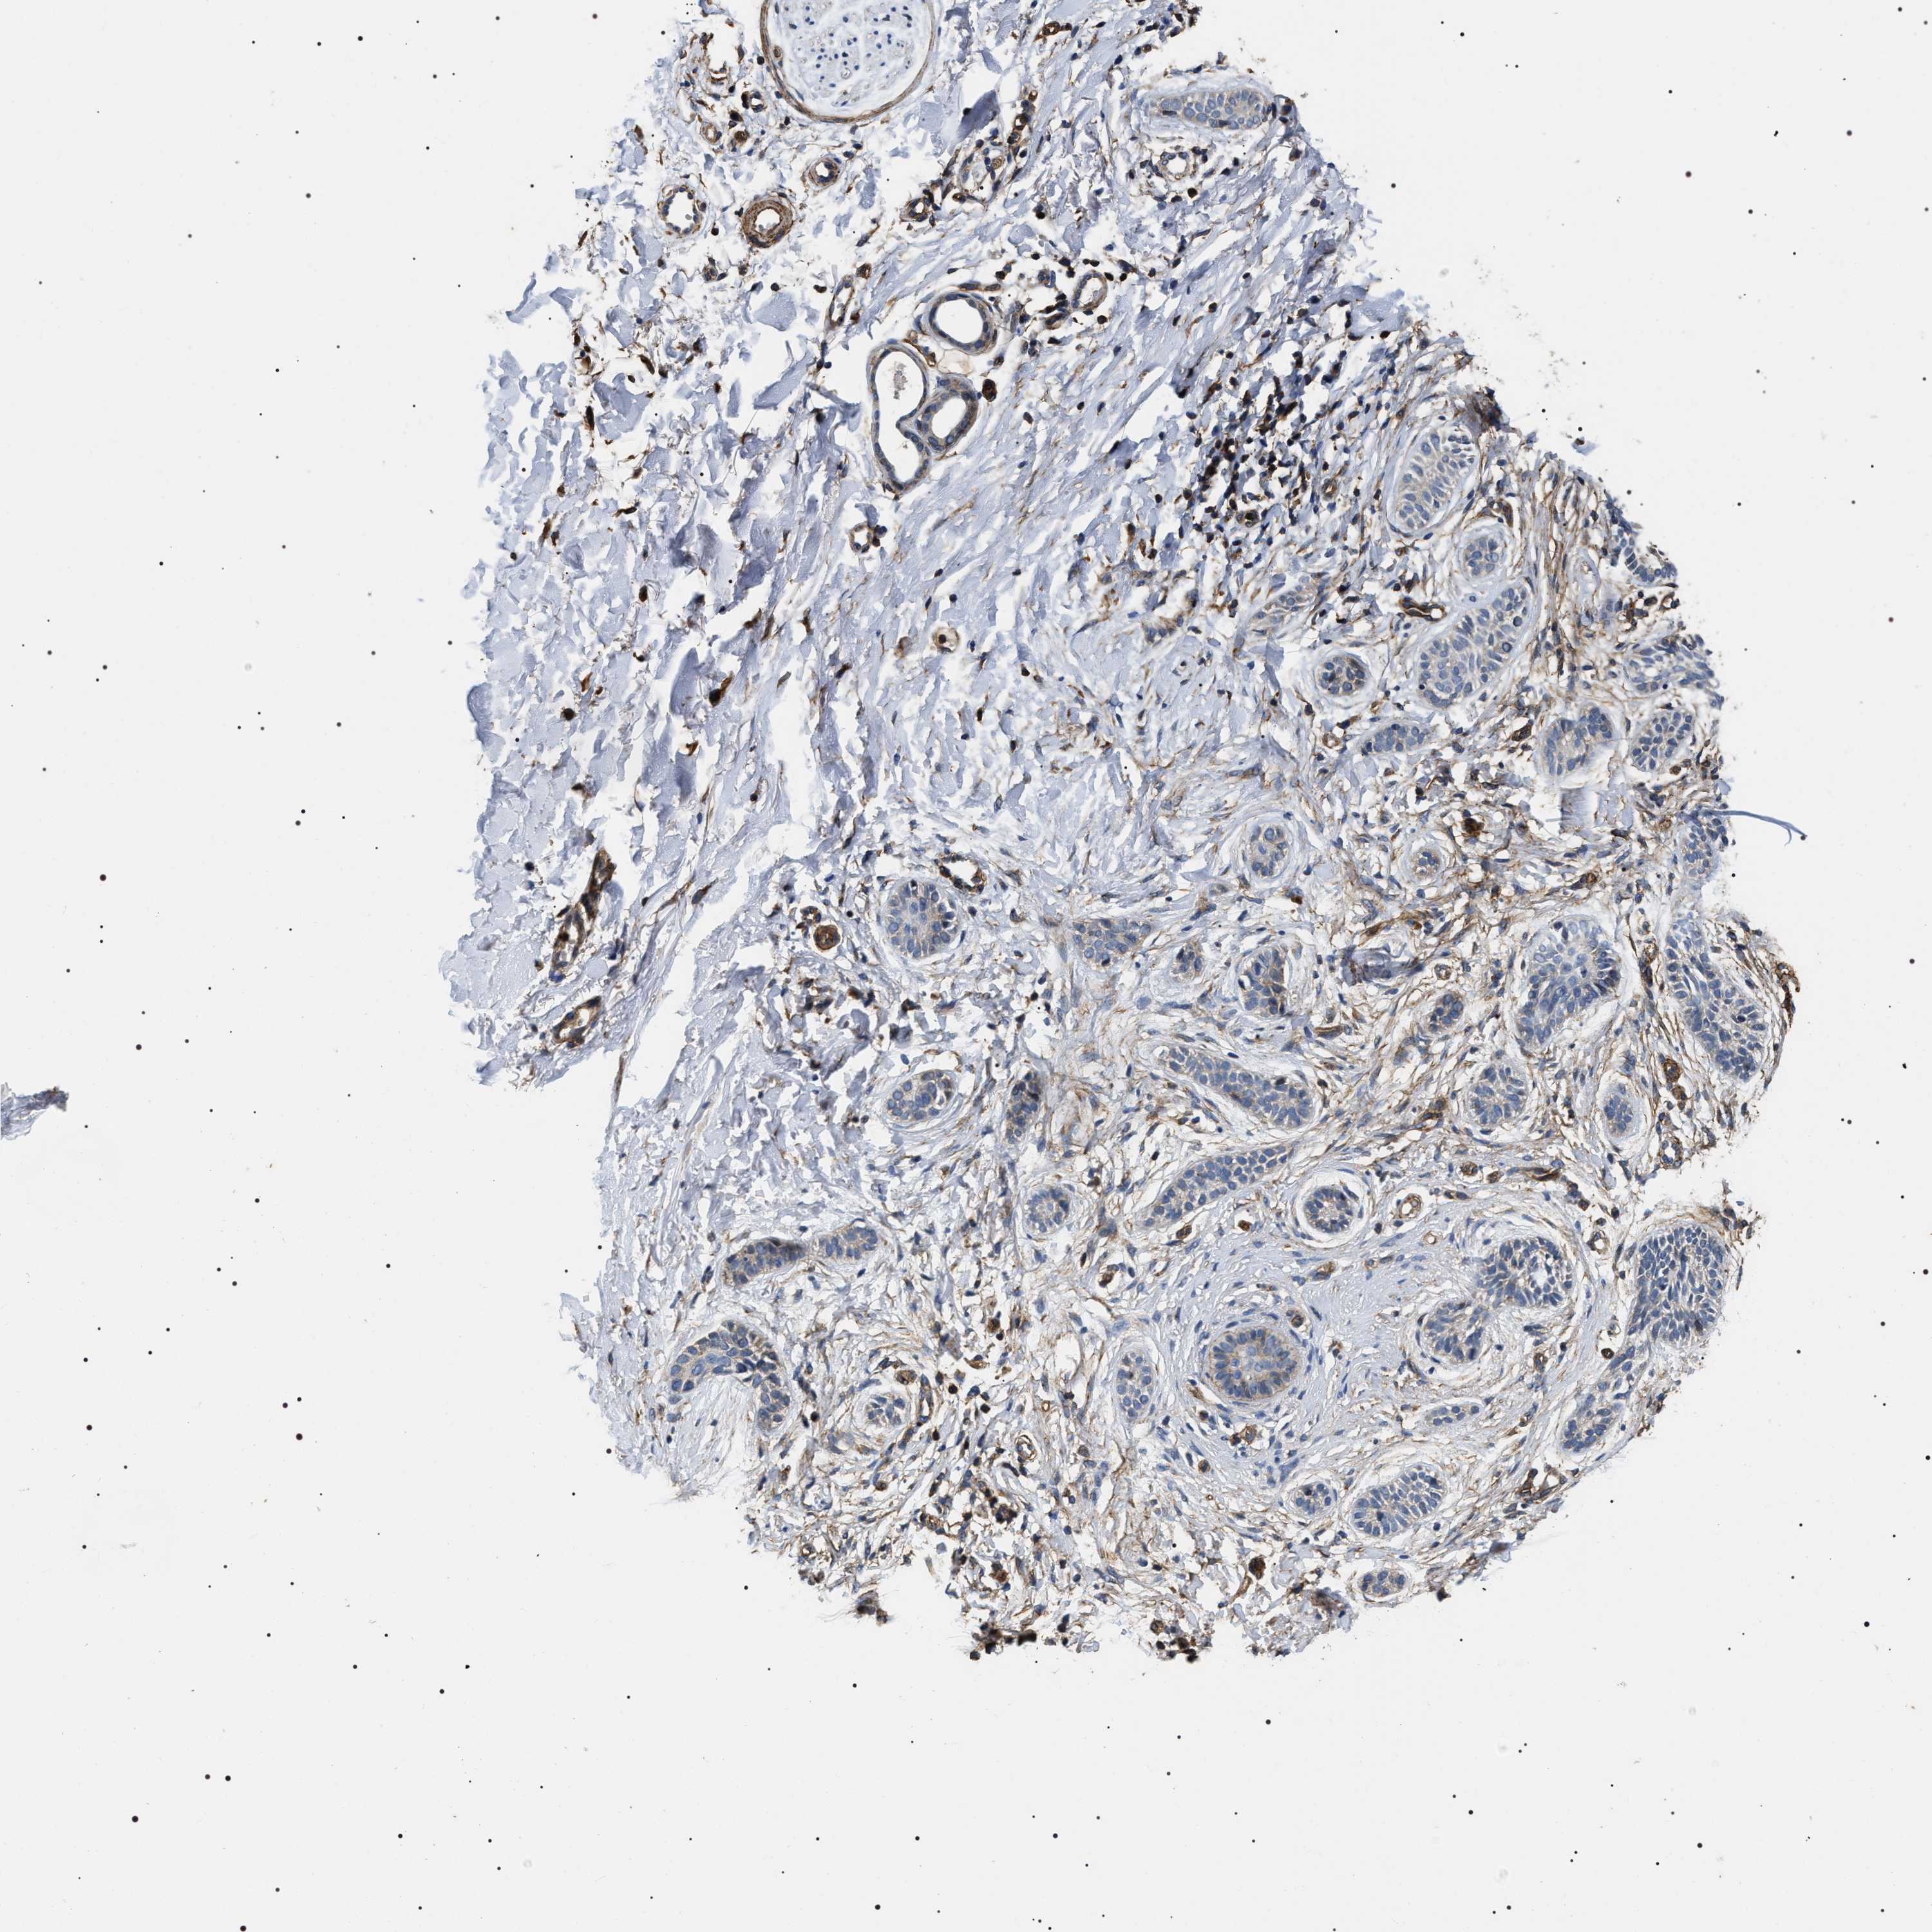

SKIN CANCER - Protein expressioni

A mouse-over function shows sample information and annotation data. Click on an image to view it in a full screen mode. Samples can be filtered based on level of antibody staining by selecting one or several of the following categories: high, medium, low and not detected. The assay and annotation is described here.

Antibody stainingi

Antibody staining in the annotated cell types in the current human tissue is reported as not detected, low, medium, or high, based on conventional immunohistochemistry profiling in selected tissues. This score is based on the combination of the staining intensity and fraction of stained cells.

Each image is clickable and will lead to virtual microscopy that enables deeper exploration of all samples and also displays staining intensity scores, fraction scores and subcellular localization as well as patient and tissue information for each sample.

Antibody HPA020386

Staining

High

Medium

Low

Not detected

Intensity

Strong

Moderate

Weak

Negative

Quantity

>75%

75%-25%

<25%

None

Location

Nuclear

Cytoplasmic/membranous

Cytoplasmic/membranous,nuclear

Squamous cell carcinoma, NOS